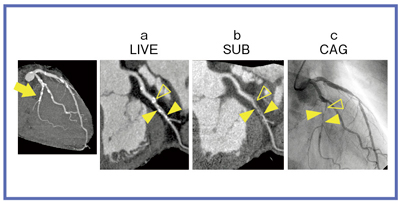

CT冠動脈造影実践学 | 木原康樹, 栗林幸夫 |本 | 通販 | Amazon, 冠動脈コンピュータ断層撮影装置(冠動脈CT),

冠動脈コンピュータ断層撮影装置(冠動脈CT), CT冠動脈バイパス術後解析 | 映像情報Medical,

CT冠動脈バイパス術後解析 | 映像情報Medical, 320列面検出器CTによる新しい冠動脈CT技術 吉岡邦浩(岩手医科,

320列面検出器CTによる新しい冠動脈CT技術 吉岡邦浩(岩手医科, 冠動脈疾患における CT-SPECT Fusion Imagingの有用性―ziosoft